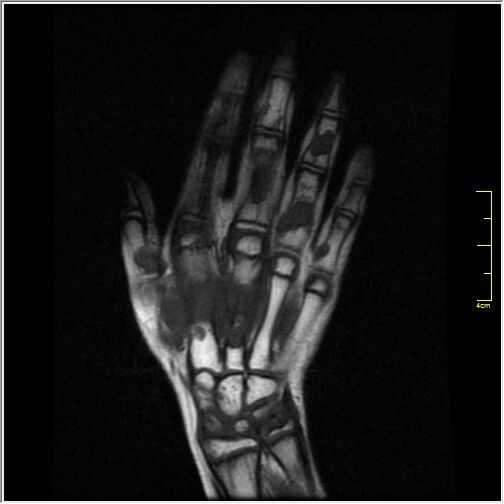

Welche Befunde erheben Sie auf dem vorliegenden Röntgen und MRT der Hand (T2fs und T1)? Verdachtsdiagnosen?